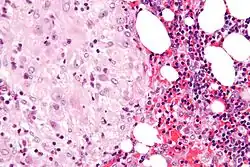

The decidua has a histologically-distinct appearance, displaying large polygonal decidual cells in the stroma. These are enlarged endometrial stromal cells, which resemble epithelium (and are referred to as "epithelioid").

-

Acute choriodeciduitis, with neutrophils seen in the chorion and decidua.